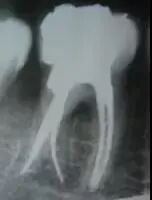

最后来玩一个根管治疗质量的评估——下图是武大彭彬教授的一个病例,仔细观察可以挑出一点问题,但问题事出有因!看看你的“眼力”如何——问题在哪里?教授的专业水平是不用怀疑的,那么事出的原因可能是什么?

1、 开髓 洞型是否制备的符合要求,髓室顶是否揭得刚刚好,没有破坏洞壁及洞底结构。 图1、裂钻钻到近髓 图2、球钻穿髓 图3、小号锉探查根管口 图4、球钻揭髓顶 图5、修整洞型 图6、完成开髓 2、 去腐 根管预备之前是否将窝洞的腐质完全去除,避免在根管预备过程中将冠部污染带进根管; 3、 根管口的直线通道 特别对于弯曲根管!预备根管之前是否重视这个环节,尽管找到了根管口,锉也能顺利进入根管,但根管口的直线通道是否建立也是衡量医生操作技能的重要依据。方法很多:手动器械操作时我们可以采用价格便宜的“GG”钻,PROTAPER 机动预备时可以采用 SX 锉。 1、弯曲根管冠部处理之前; 2、用GG钻或SX锉进行预备; 3、处理后形成的直线通道 我的病例1_____冠部处理成直线通道后的充填效果 我的病例2_____下颌7"C"型根管的充填效果 4、 疏通中下段根管 要用小号锉 08和10号 K锉进行探查,手法是用顺反30度来回搓动的方法进入,建立根管中下段的预备通道,然后换用15号 K锉进行疏通,便于大号不锈钢器械或镍钛器械的进入。 5、 确定工作长度 15号 K锉进入时最好配合根测仪;术前,术中,术后都要拍X—RAY。 6、 冲洗方法 每次换锉之前及都要进行,但是否有效往往是不确定的,因为冲洗的效果和多方面因素有关——小号的针头(如果没有专用的针头可以用皮试的小针头),“双次冲洗法(自命名)”——即每次冲洗完毕后再用小号锉(如10号或15号)进入根管下段捣动一番,让碎屑随着冲洗液浮出根管中上段,然后进行二次冲洗,这样就能将根管内的碎屑清除彻底!注意头次冲洗后不要清除根管内的冲洗液,它的存在有非常重要的作用! 7、 建立根充档 根尖部牙本质和牙骨质的交界处不要破坏,这对后期的根充以及主尖的选择很有意义,前提是每次预备都要明确的把握工作长度! 8、 弯曲根管最好采用不锈钢锉同镍钛锉配合使用 用不锈钢器械预备弯曲根管中下段,镍钛器械预备中上段! 9、 "冠根方向”预备是可取的方法,但有些时候还是需要结合“逐步后退法"使用的。 10、 熟悉使用器械的性能及各类操作方法的临床要点 逐步后退法预备存在的一些问题——A,根管锉与根管壁接触面积大(锉进入时困难;容易被卡住;器械容易折断;碎屑容易被推向根尖区;锉尖不好控制。);B,根管成形受限(根尖区冲洗困难;碎屑清除困难;碎屑容易推出根尖孔以外引起根尖症状。)C,需要频繁换锉(操作繁琐;临床操作时间长。)因此,很多牙医已经不采用该法,取而代之使用的是采用镍钛器械进行冠根向预备法“Crown Down”。但不锈钢器械(如K锉)还是有它的用途——小号K锉可以用来寻找根管以及进行根管疏通;用来确定工作长度;用来进行根尖预备;弯曲根管配合镍钛器械进行预备比较安全! 问题答案:这个病例的问题主要反应在开髓的洞形修整,注意观察该牙X-RAY的左侧洞壁,如果常规情况制备成这样是由于裂钻破坏了洞壁和洞底所形成的台阶。如果评估根管治疗的质量那是要扣分的!但这个病例仔细观察洞壁形态就可以看出:该病例属于再治疗的病例,因此还是属于一个理想的病例。 图文来源网络,版权属于原作者 转载只为分享,如有侵权,请联系删除 扫一扫 | 客服微信 了解更多 | 行业招聘资讯 - 医招职达 - 让人才更有价值 做精准高效的口腔人力资源服务平台